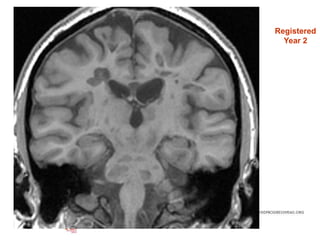

Registered

Year 2

• #42 Repeat scans – registered to baseline (spatially aligned)